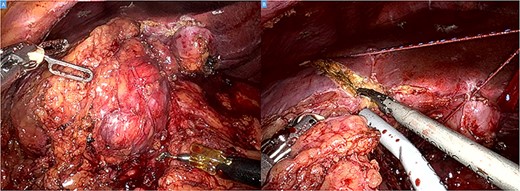

The operation was performed using the Da Vinci Xi system. Initial exploration showed a large and bulky lesion in the liver’s segments V–VI completely fused to the right colonic flexure (Fig. 3A and B).

Intraoperative picture showing a bulky tumor infiltrating the liver’s segments V–VI and the right colic flexure (A). Hepatic transection with the harmonic (B).